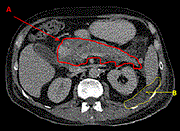

Pancreatic neuroendocrine tumor featuring growth into the main pancreatic duct and tumor thrombus within the splenic vein: a case report

Takashi Miyata and others

Journal of Surgical Case Reports, Volume 2020, Issue 7, July 2020, rjaa155, https://doi.org/10.1093/jscr/rjaa155